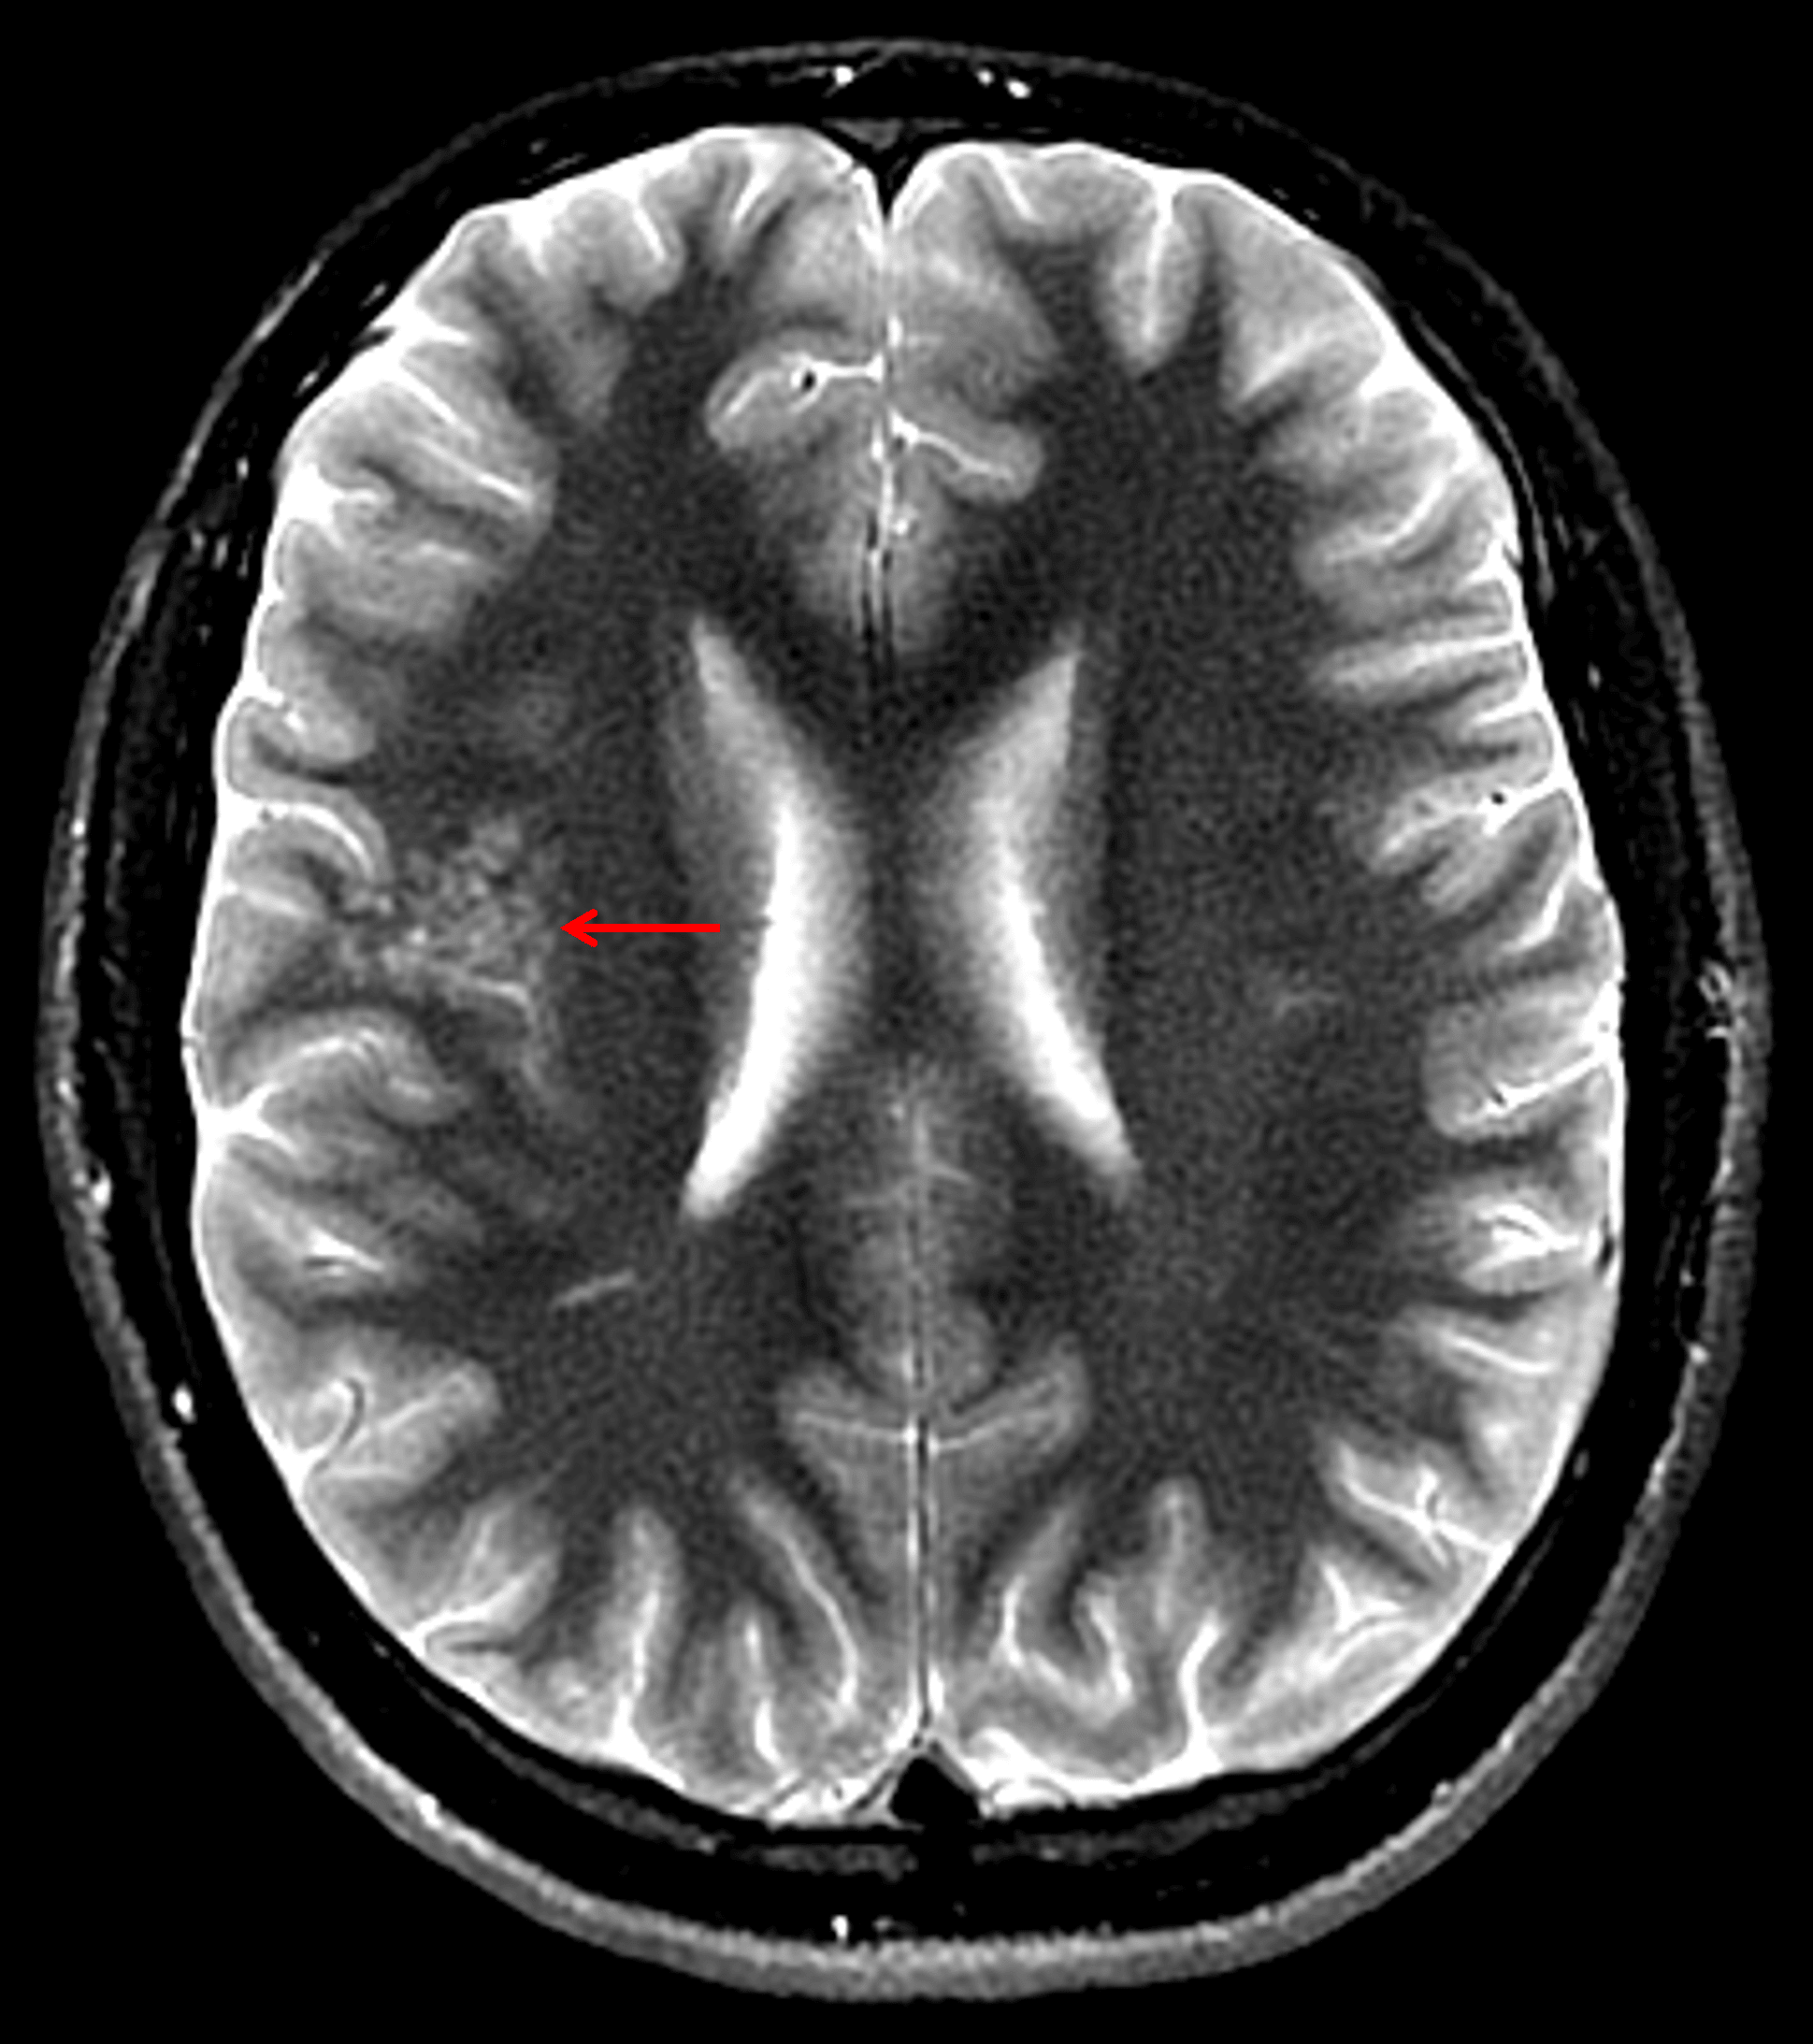

Clustered T2 hyperintense cystic structures in the subcortical white matter of the right frontal operculum and superior insula (red arrow) with normal appearance of the overlying cortex which is a typical appearance for MVNT.